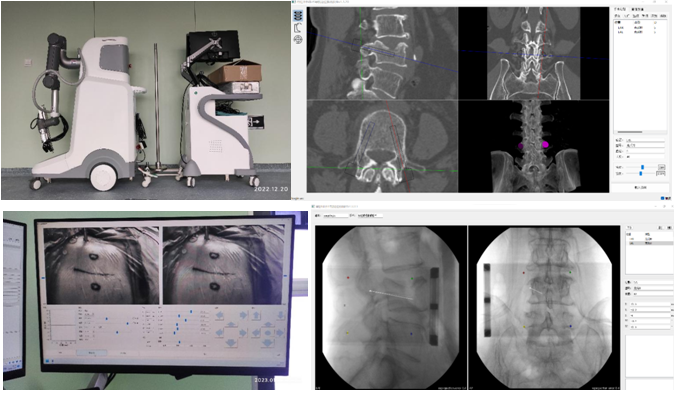

机器人辅助技术是脊柱外科手术向智能化、精准化、微创化发展的又一次飞跃。1月10日,刘时璋主任带领骨科团队精诚合作,在手术室、麻醉科及消毒供应室的鼎力协助下,成功开展六合彩网站

首例机器人辅助局麻下“经皮球囊扩张椎体成形术(PKP)”治疗腰椎压缩性骨折。此例手术较传统的徒手穿刺更为精准、安全、高效,体现了数字医学与骨科智能化的融合发展。

经MRI及CT检查示:腰4椎体压缩性骨折。经专家讨论后,医疗团队拟采用机器人辅助,局麻下行经皮球囊扩张椎体成形术。经过精密的仪器调试和配准,术前进行了反复的模型演练。刘时璋主任团队将患者的CT数据与机器人系统配准,工程师团队将事先规划好的个体化穿刺路径数据植入机器人系统。将术中的正侧位X线透视数据与CT数据融合后,机械臂按照术前规划路径,一次性穿刺成功,位置精准满意。